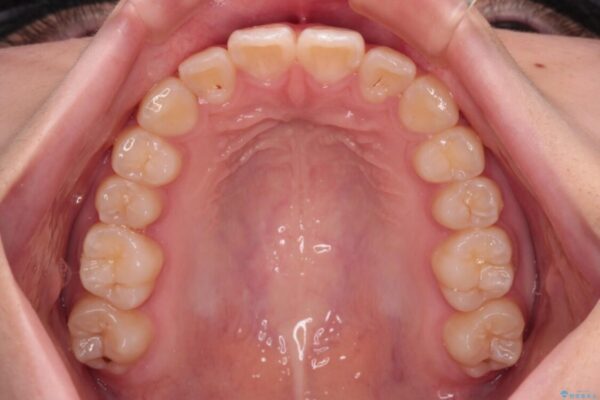

治療後

• インビザラインは使える自信がない ワイヤー装置にて矯正治療 治療後画像